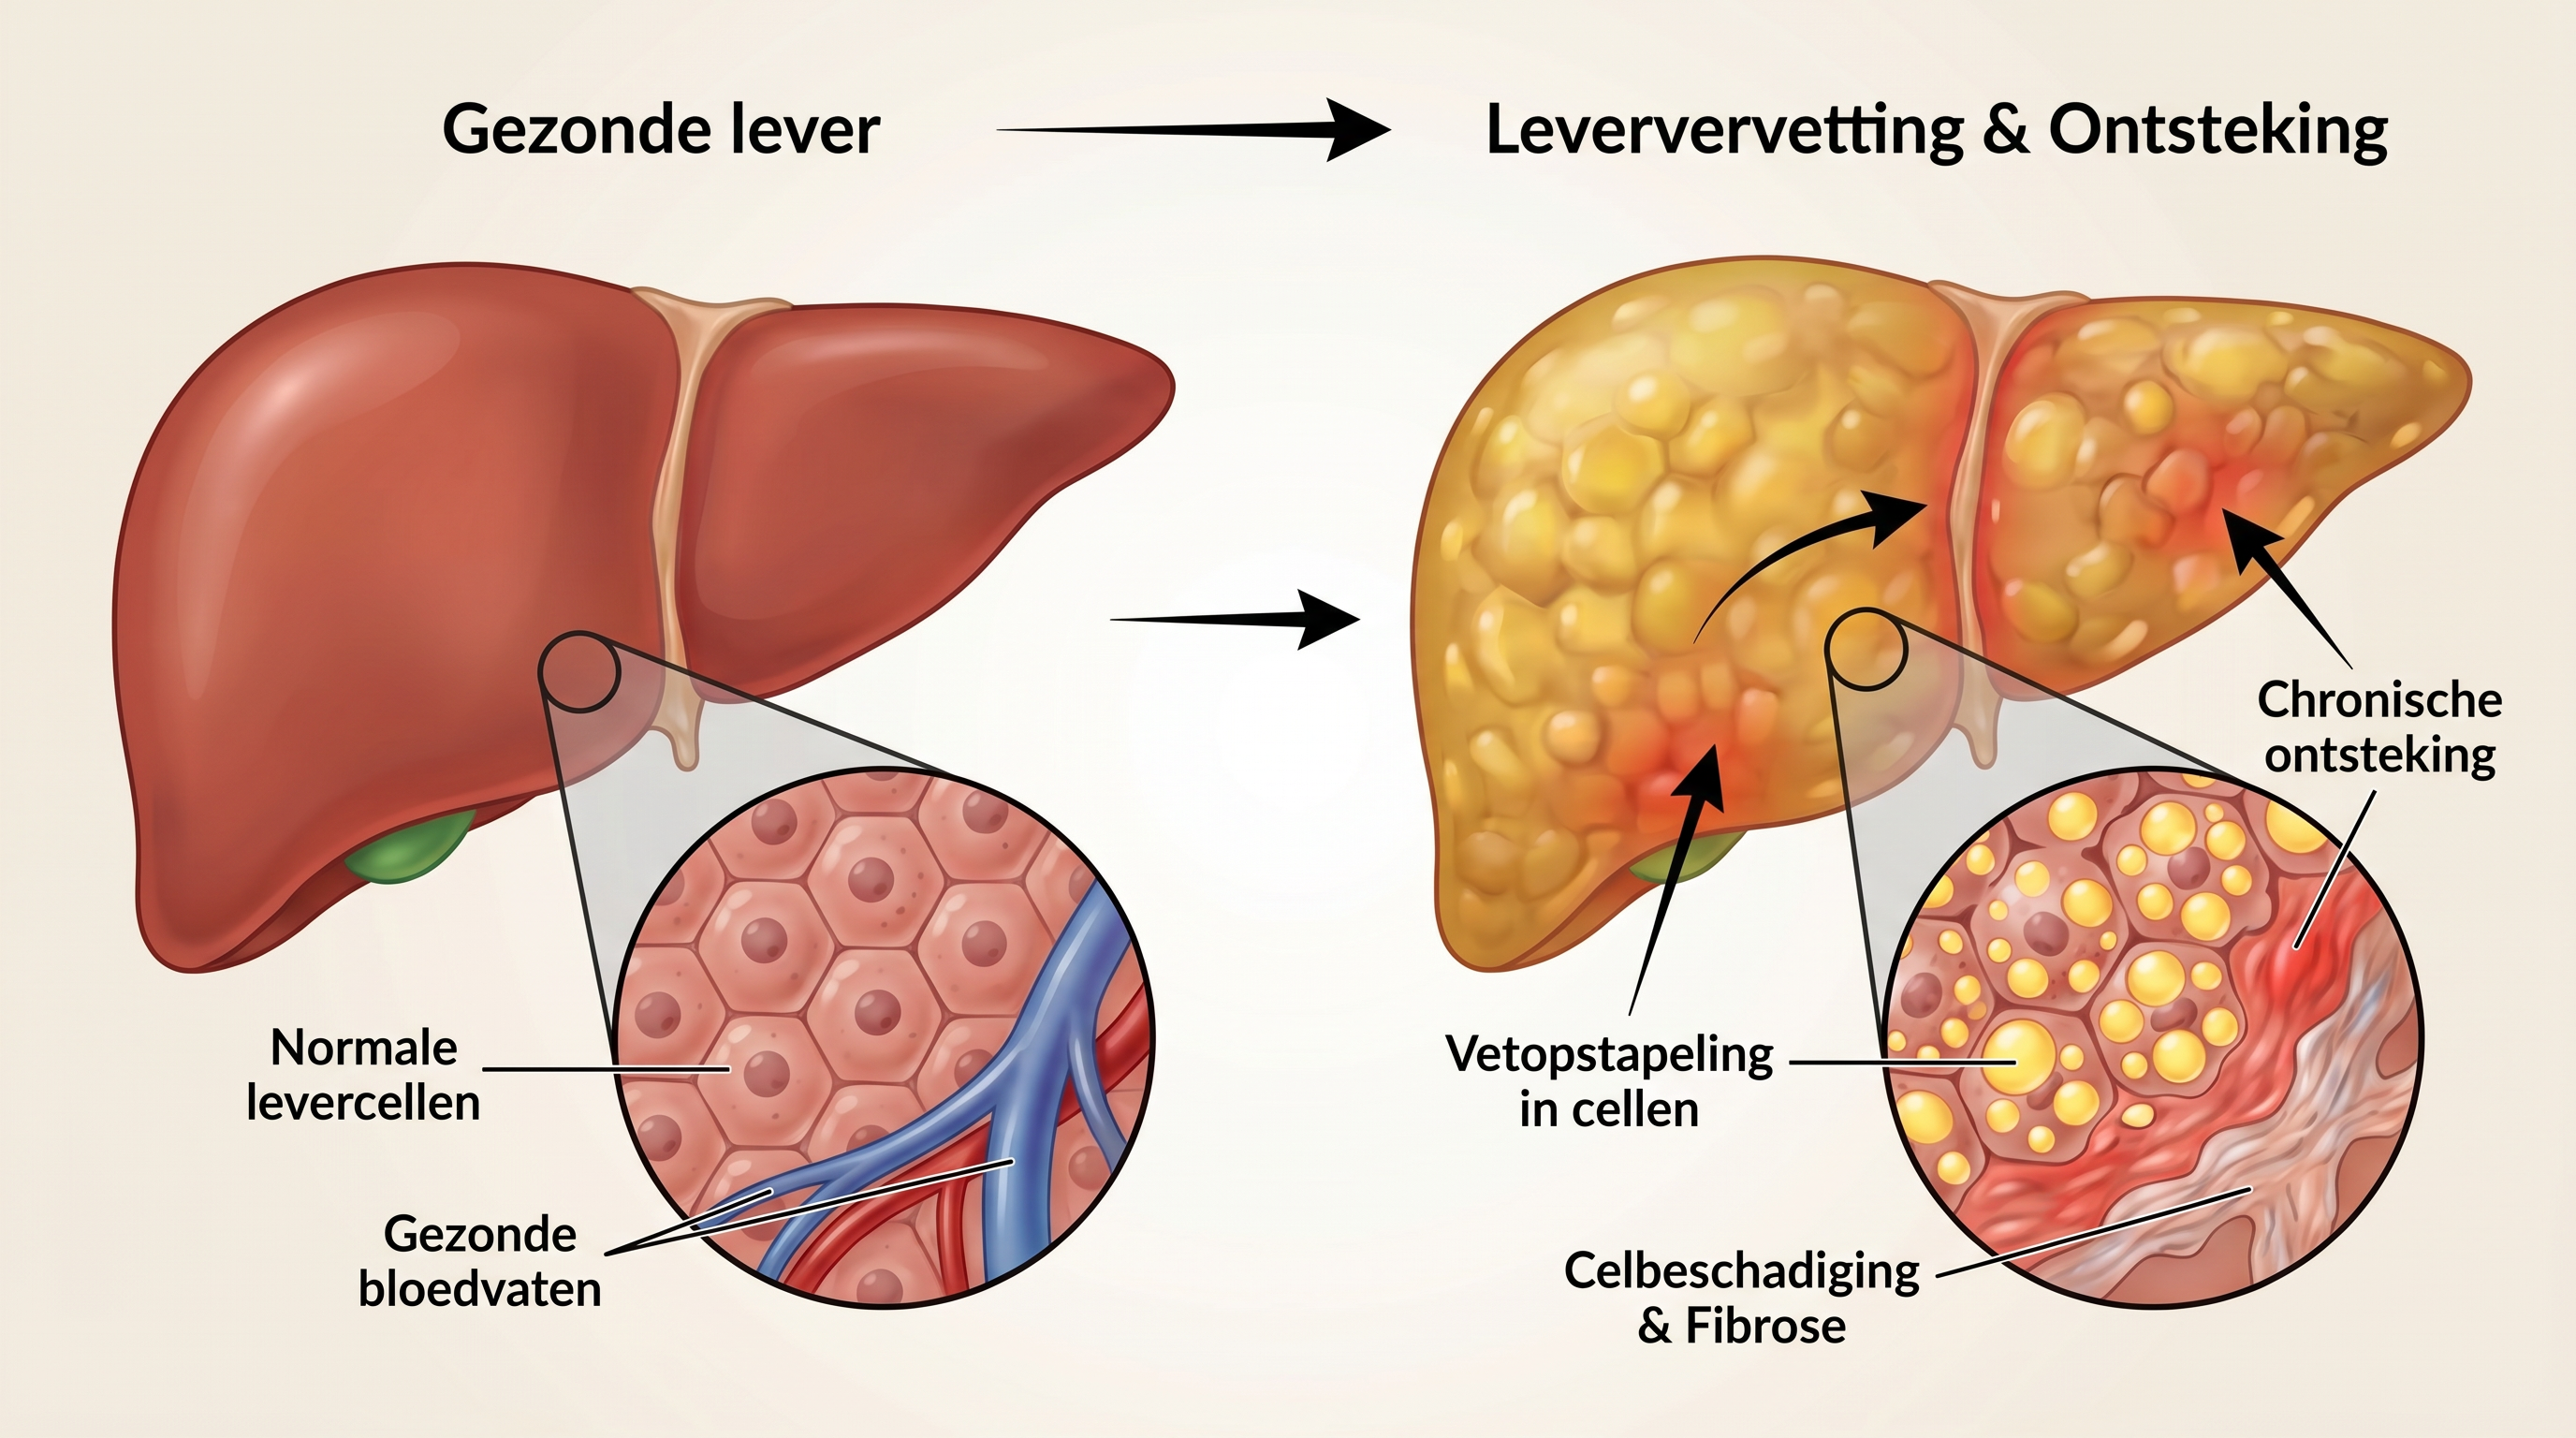

Om het verschil te begrijpen, moeten we eerst begrijpen hoe de lever vet verwerkt en wat er misgaat bij leververvetting.

De lever verwerkt normaal gesproken vetten efficiënt — maar wanneer er meer vet binnenkomt dan de lever kan verwerken, begint het overtollige vet zich op te stapelen in de levercellen zelf.

Een gezonde lever met een goed functionerend metabolisme verwerkt vetten soepel en houdt de leverenzymen binnen normale waarden.

Kijk nu naar een aangetaste lever.

Door vetopstapeling raken levercellen beschadigd — de kleine vetdruppeltjes in de cellen verstoren de normale leverfunctie, veroorzaken oxidatieve stress en activeren ontstekingsreacties die de schade verder uitbreiden.

Het is als een overbelaste fabriek die haar eigen afval begint op te slaan.

Op een gegeven moment raakt het systeem verstopt — en begint de schade zich uit te breiden naar het omliggende leverweefsel.

Vanaf je 40e neemt de gevoeligheid van je cellen voor insuline geleidelijk af — insulineresistentie zorgt ervoor dat de lever meer vet aanmaakt en minder efficiënt afbreekt.

Chronische laaggradige ontsteking — mede veroorzaakt door buikvet, bewerkte voeding en stress — versnelt dit proces dramatisch.